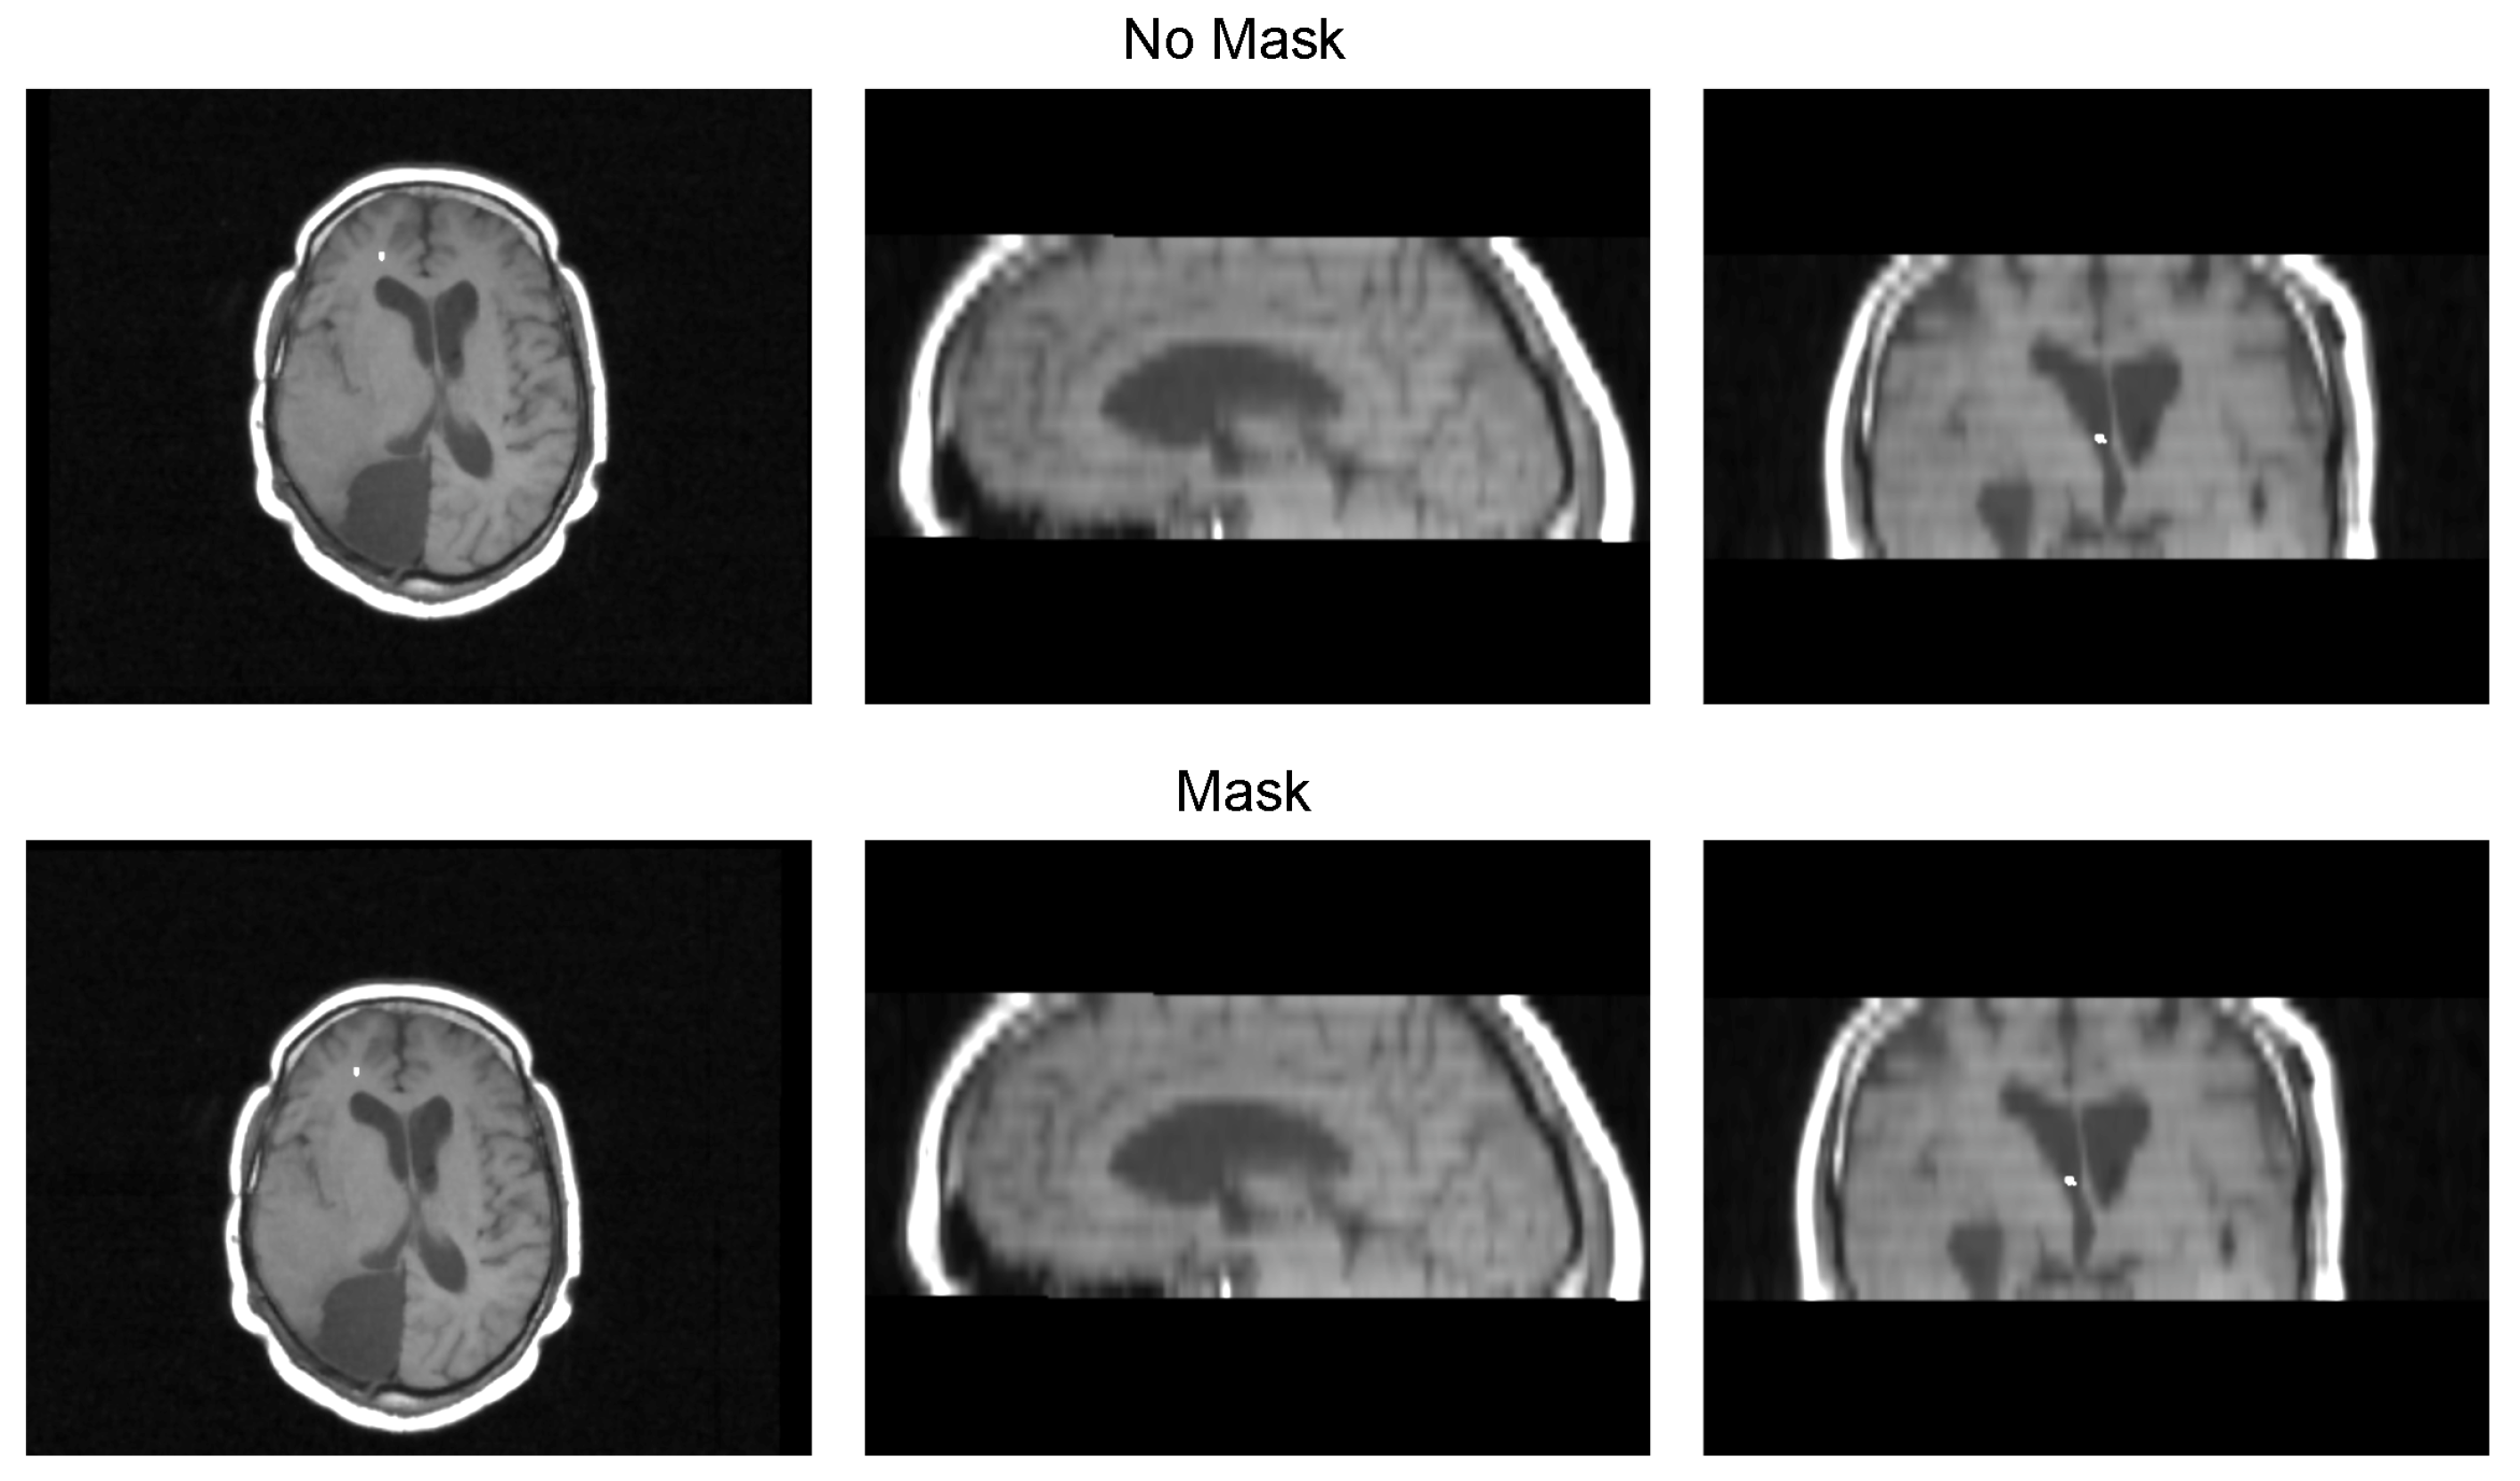

We validated the performance of the fusion method following the two methodologies in Section 3. We used eight pairs of CT and MRI from the RIRE dataset for the first method. The CT images were generated with the method described in Section 3.1.1. We compared the procedure shown in Figure 8 against a fusion procedure that does not employ a sampling mask of the brain tissue, which is shown in Figure 9. Both methods used a rigid registration with MI as the similarity metric and gradient descent for the optimization. We used descriptive statistical metrics of central tendency and variation to compare the methods using the validation from Section 3.1. These results were summarized in the box plot shown in Figure 10. For the second validation, we faced a limitation in the number of images available for evaluation. Given this constraint, we opted to compare the methods individually for each of the four cases. A scatter plot was chosen as the most suitable representation to visualize the error dispersion for both methods. Scatter plots are particularly effective in such scenarios as they allow for clear visualization of individual data points, making it easier to discern patterns or anomalies, especially when dealing with a smaller dataset. This approach provides a more transparent and detailed view of the distribution of errors across the limited set of images. The results of this comparison are illustrated in Figure 11.

Table 3 displays the Euclidean distance between the reference points and the resulting points of the transformation from the compared methods. From the data, we can observe that the difference in the Euclidean distance for our method is significantly lower in images 3, 6, and 8. This is mainly caused by the differences in the original images that have some variations in brain tissue, as shown in Figure 12, Figure 13 and Figure 14. Due to some electrodes passing through these areas with variations, the sampling in the registration does not use these voxels to compute the transformation, thus improving the registration when the mask is used. The results are represented in Figure 10, where our method using a sampling mask yields a Euclidean distance of 1.3176 mm with a standard deviation of 0.8643. In contrast, the method without a sampling mask yields a Euclidean distance of 1.2789 mm with a standard deviation of 5.2511. These findings suggest that the use of the mask improves the registration when there is a great difference in the tissue between the MRI and CT images due to the reduction in voxel sampling of these varying tissues in the registration process.

Figure 12. Image 3 fusion with no mask and with a mask.

Diagnostics 13 03420 g012